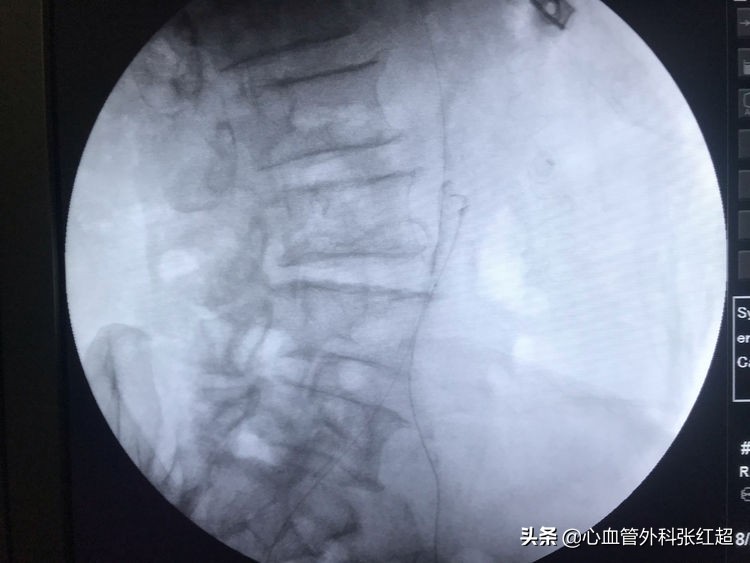

●LCIA闭塞全程闭塞病变

●治疗的结点:

➢左侧股动脉无搏动

➢正常股动脉长度不够支撑动脉鞘

➢闭塞长度超过10cm

➢闭塞时间长

➢LCIA平头闭塞,不仅无法翻山,而且如果扩张,很可能影响对侧髂动脉血流。

1.研究CTA,骨标和钙化。

2.细微搏动。

3.对比对侧解剖。

4.细针引导。

5.严格控制导丝和导管深度。